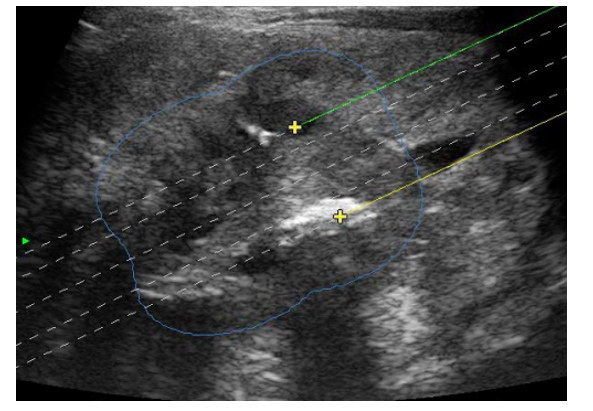

Widzimy tutaj na przekroju histologicznym obszary martwicy i proszę zobaczyć schematycznie jak wygląda ta metoda. Pod kontrolą USG widzimy dokładnie gdzie wprowadzone są igłę do guzka, gdzie wprowadzone są światłowody i obserwujemy obszar tkanki ablowanej.

Pod kontrolą USG w czasie rzeczywistym

Tak wygląda to śródoperacyjnie. Jak mówiłam Państwu wcześniej wprowadzamy najczęściej jedną lub dwie igły, jedną lub dwa światłowody z znieczulenia miejscowego.

Poniżej można zobaczyć jak wygląda obraz śródoperacyjny na ekranie USG.

Jest to metoda, która pozwala nam zaplanować wcześniej potencjalne obszary ablacji, ale też weryfikować w czasie rzeczywistym co dzieje się w USG, co daje nam operatorom pełną kontrolę nad tym co robimy, a pacjentowi daje bezpieczeństwo.